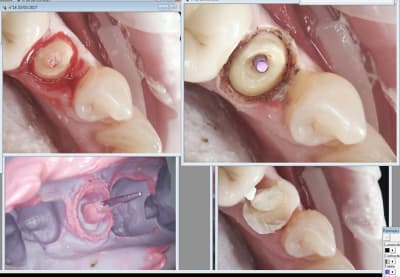

Capture d écran 2017 03 16 17.29 - Eugenol

Capture d écran 2017 03 16 17.27 - Eugenol

Capture d écran 2017 03 16 13.05 - Eugenol

Prépa juxta gingivale puis un coup dans le sulcus. Par contre j'y mets de l'expasyl après un réflexe. ( en principe pas nécessaire)

Pas de douleurs per op sans anesthésie ( attention à 0,8 watt) donc post op ca m'étonnerait. Rétractation aussi ca m'étonnerait. ( mais bon je vais poser les premières la semaine prochaine). J'ai pas eu de coup de fil de patients pour l'instant. -)

Celle la ca saignait un peu. -)

Il faudrait que j'arrete de préparer trop sous gingival. Un réflexe à perdre.

Tiens suite de mon Ic à 4 pattes empreinte prise le 9 03 et pose aujourd'hui. Aspect de la gencive encourageant après le coup de laser.